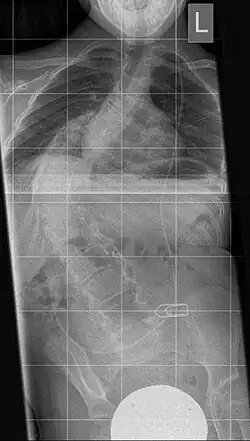

Thoracic scoliosis due to Diastematomyelia and Myelomeningocele (MMC) in a 10-year-old boy

The instrument is used to dilate a too small or too narrow rib thorax in severe thoracic deformity. It consists of a telescopic "titanium rib" in curved form with several holes in a row for fixing in the desired length. A prolongation can be carried out after 6 months. The fixation takes place between two ribs or between a rib and the iliac crest. This results in an indirect erection of the deformed spine, resulting in an increase in the volume of the thoracic cavity along with the lung.